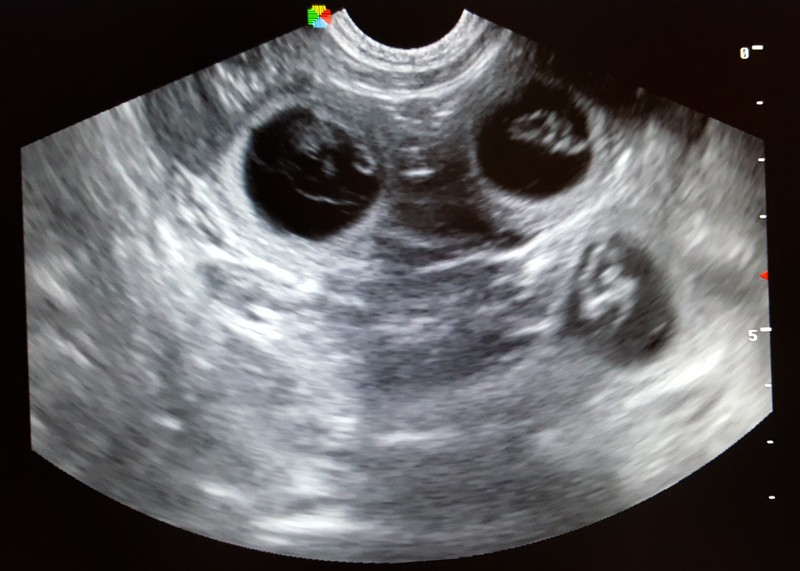

28. dubna 2017 - Cindynka má potvrzenou březost !

Podle ranní sonografie má naše nejmladší fenka v bříšku minimálně 5 štěňátek.![]()

A jelikož už trochu víme, jak to chodí, dá se čekat početný pátý vrh z Borových lesů.